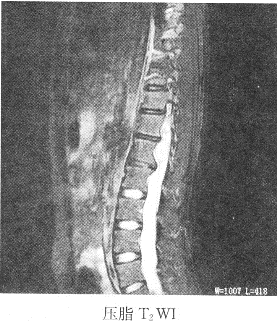

患者女性,23岁,两下肢感觉麻木,结合图像,最可能的诊断是()A: 胸髓积水B: 胸髓血肿C: 室管膜瘤D: 神经鞘瘤E: 椎管内脂肪瘤

患者女性,23岁,两下肢感觉麻木,结合图像,最可能的诊断是()

- A: 胸髓积水

- B: 胸髓血肿

- C: 室管膜瘤

- D: 神经鞘瘤

- E: 椎管内脂肪瘤